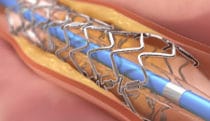

DES that mimics vessel function

Animation -

Stent deployment

Illustration -